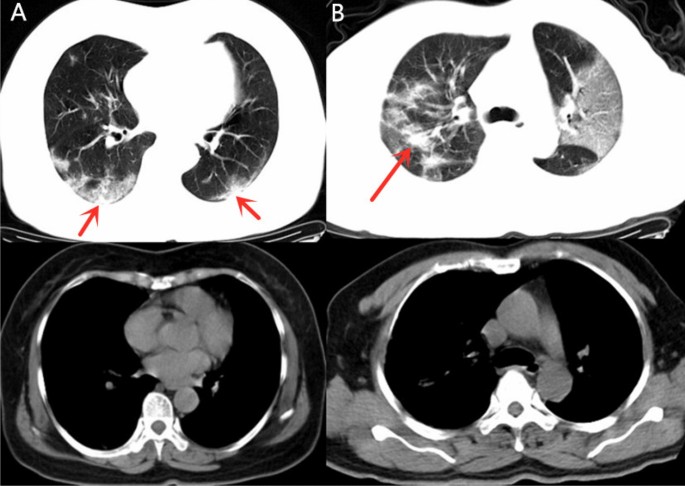

The demonstration of GGO components more than consolidation (Fig. 4) was higher in group 1 (24, 25.0%) than in group 2 (8, 10.5%), with a significant difference between the groups (p = 0.015). The demonstration of consolidation components more than GGO (Fig. 5) was higher in group 2 (54, 71.1%) than in group 1 (50, 52.1%) with significant difference (p = 0.012). The morphological features, including the presence of patchy shadowing (p = 0.286), and linear shadowing (p = 0.558) exhibited no significant difference between groups 1 and group 2.

Example of patients with CT demonstrated as GGO > consolidation in Group 1. (A) 65-year-old female with confirmed COVID-19 pneumonia in Group 1 who had hospitalization time of 12 days. CT images demonstrated multiple mixed GGO and consolidation lesions with bilateral distribution, the consolidation component (arrow) was apparently less than GGO. (B) 53-year-old man in Group 1 with 12 admission days. Multiple mixed GGO and consolidation lesions with bilateral distribution were seen in his CT images, at the same time. The range of GGO components was apparently more than consolidation (arrow).